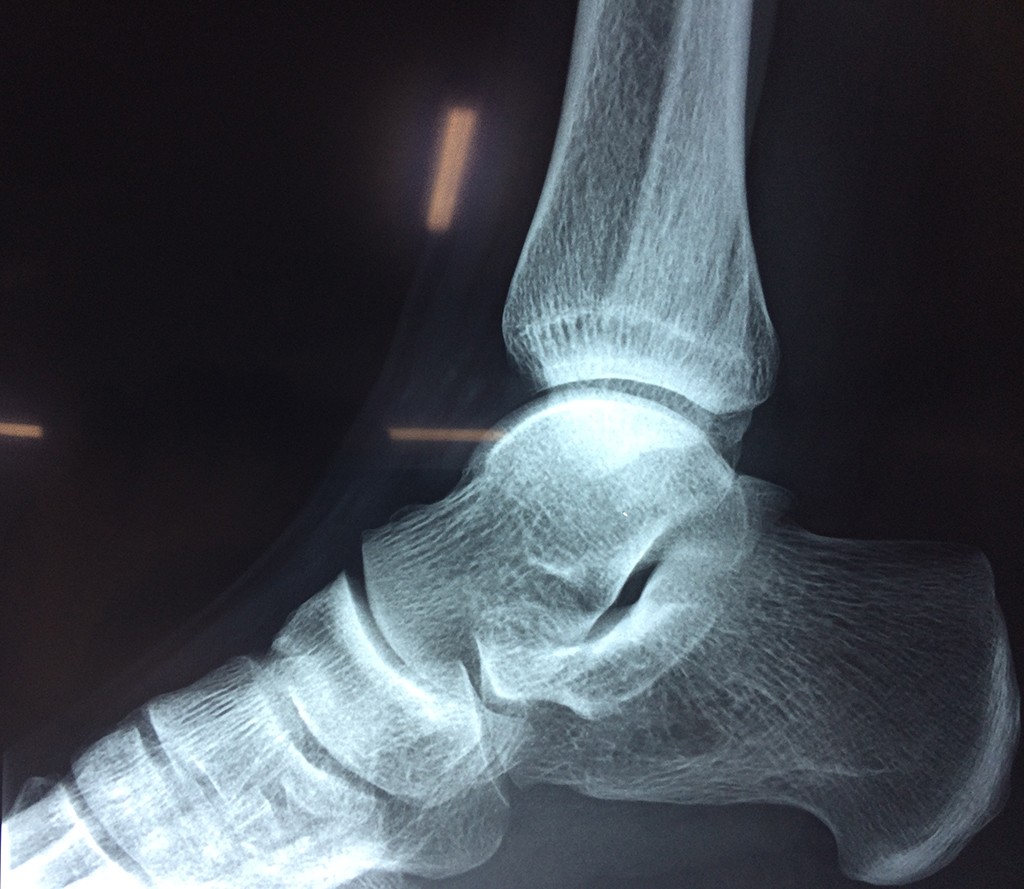

Una fractura de tobillo es la rotura de uno o más de los huesos del tobillo. Estas fracturas pueden ser:

- Producirse en uno o ambos lados del tobillo.

- La fractura se extiende hasta la articulación del tobillo (fractura intra-articular).